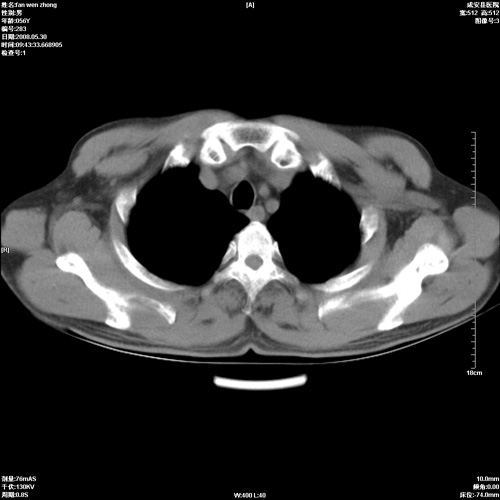

病人 男 56岁 一周前高热,体温达39-40度,经抗炎治疗后,体温渐降,达37,5-38度,轻微咳嗽,胸部不适 查白细胞为1.3万 行ct检查,请分析。

双肺内可见多发结节状病灶,并见小空洞,病人高热,白血球增高,应该是典型的迁徙性肺脓肿(多为金黄色葡萄球菌感染)。查一下口腔等其它部位有无感染灶。

双肺内可见多发结节状病灶,并见小空洞,病人高热,白血球增高,应该是典型的迁徙性肺脓肿(多为金黄色葡萄球菌感染)。建议治疗后复查.